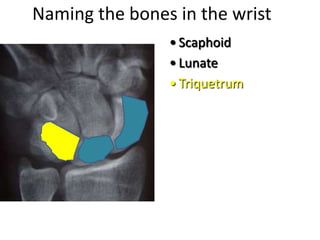

- Naming the bones, joints, tendons, nerves and skin landmarks of the hand and wrist.